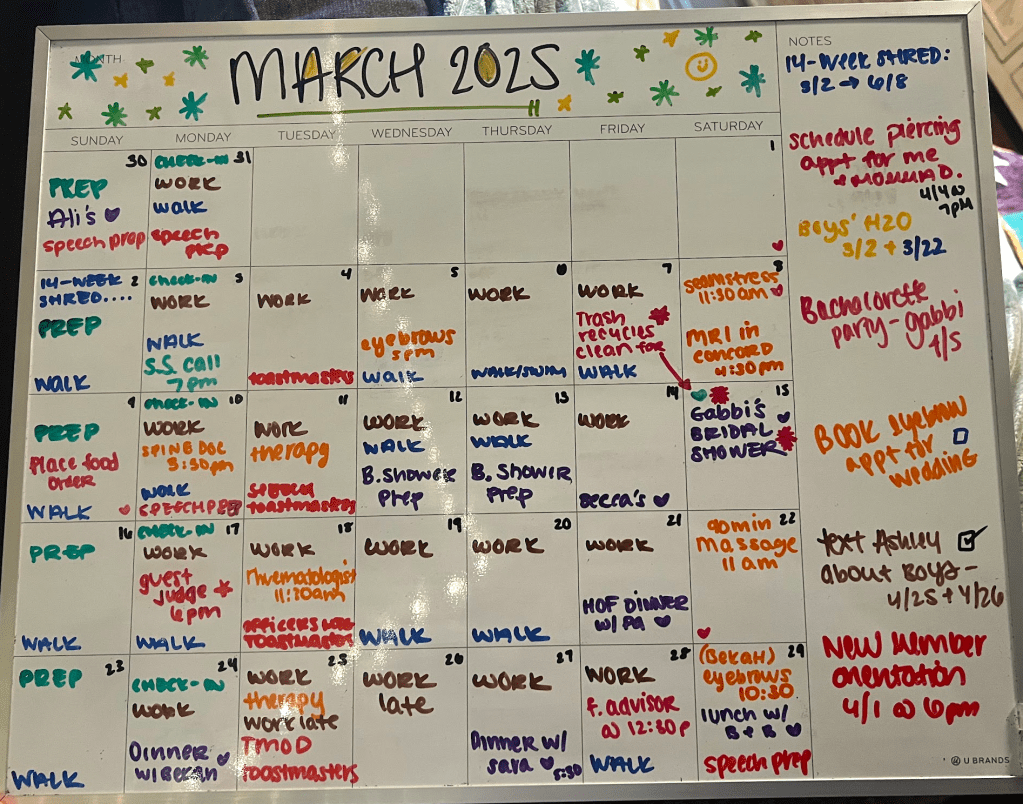

I figured the spine doctor would determine whether or not the MRI was necessary at my appointment on February 26, so you can imagine my surprise when the office called me to schedule my MRI for Saturday, March 8 at 4:30 PM (ew, but I’ll take it!).

On March 8 at 4:45 PM, I slid into the MRI tube and listened to screamo music while the machine did its thing for 15 minutes.

I was originally scheduled to review the MRI results with Dr. Rickert on March 18, but because of a cancellation, I was able to get in on March 10 (yes, the Monday after my Saturday MRI).

Once you drop the words “Ankylosing Spondylitis” (and then spell it), the front office staff at a Rheumatology office tend to move quickly, especially when it’s backed by the fact that your mom works in the same system (I mean, come on, Domenichella is not a common last name) and your referral has been updated to “Priority — within a month. Must be seen by April 10, 2025”. Woof. 🙂

At first, the only available appointment was May 6, but the sweetest woman at the front desk said she’d shoot the rheumatologist a message to explain the situation. I didn’t think anything of it and told Momma D. my appointment was scheduled for May 6. She said she was working that day, but wanted to be conferenced in.

A few hours later, the front desk lady called me back and left me a voicemail (I was in a meeting) that Dr. Goodman wanted to see me sooner than May 6 and was opening his schedule up on Tuesday, March 18 at 11:30 AM for me.

I couldn’t schedule my next set of MRIs because insurance was putting their foot down. I don’t know what happened with that because on Saturday, March 15, I got a text from the patient care coordinator that insurance was good-to-go and I could call the office on Monday to schedule the MRIs. I’m not going to ask questions!

Well, I’ll spare you the details but insurance got involved again and after 70 minutes on the phone with them trying to get me to go elsewhere for my MRIs and it getting nowhere, Momma D finally said, “Let’s see what Dr. Goodman says tomorrow. He might not think you need any additional imaging done”.